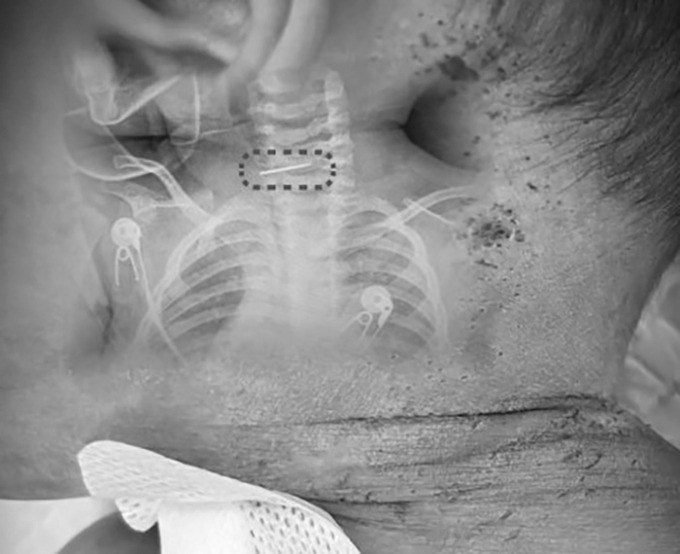

Theo báo cáo của SCMP, bác sĩ Sui ước tính đứa trẻ đã bị đâm khoảng 600 lần. Hình ảnh được ghi lại cho thấy nhiều vết đâm và các mảng vảy sẫm màu xuất hiện khắp bàn chân, đầu và thân mình của bé trai.

Bé trai bị nhiều vết kim đâm khắp cơ thể. Ảnh: Red Star News

Bác sĩ Sui cho biết ca phẫu thuật gặp nhiều khó khăn do cha mẹ không xác định được hình dạng chính xác của cây kim, cũng như việc kim có ngạnh hay không. Việc rút kim sai hướng có thể khiến đầu kim móc vào các mô khác và gây tổn thương nghiêm trọng.